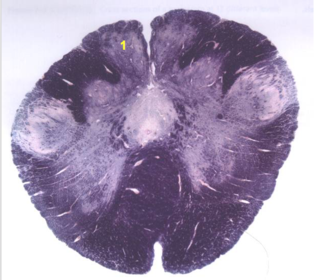

| Nucleus gracilis | |

| Accessory nucleus | |

| Medial longitudinal faciculus | |

| Pyramidal decussation | |

| Medullary pyramids | |

| Anterior spinocerebellar tract | |

| ALS | |

| Posterior spinocerebellar tract | |

| Spinal tract of V | |

| Spinal nucleus of V | |

| Nucleus cuneatus | |

| Fasciculus cuneatus | |

| Fasciculus gracilis | |

| Central canal | |